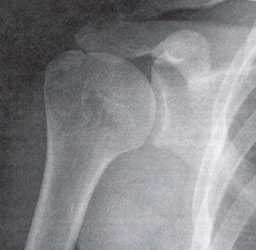

Импинджмент-синдром.а. МРТ плечевого сустава, б. рентгенография плечевого сустава.

- Рентгенография плечевого сустава. Базовое исследование с достаточно низкой информативностью. Позволяет исключить некоторые патологии, установить размер субакромиального пространства, обнаружить остеофиты и участки кальцификации в мягких тканях.

- МРТ плечевого сустава. Назначается для подробного изучения мягкотканных структур: вращательной манжеты, сухожилия двуглавой мышцы, суставной губы. Обнаруживает даже незначительные дефекты (надрывы) признаки дегенерации и воспалительного процесса.